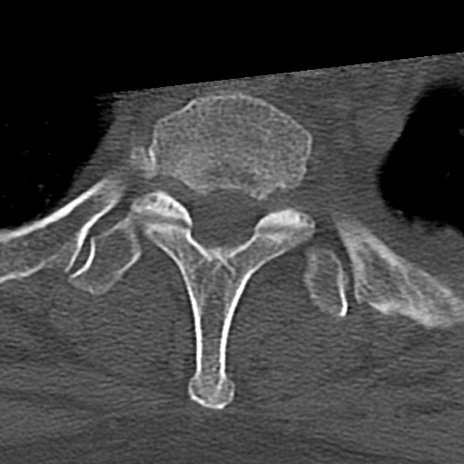

頚椎CT

横断像